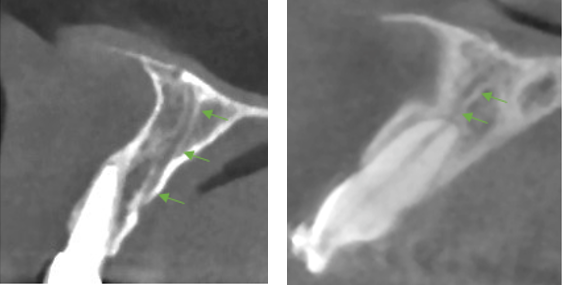

The data of 18 adolescents was described (7 males and 11 females). The age group ranged from 7 to 18 years (mean age=15.8 years). Eight cases presented at least 1 AC (44%) and a total of 15 ACs were identified, with only 3 cases showing an AC with a foramen width greater than 1mm (16.7%, 95% confidence interval [3.6%; 41.4%]) see Table 5 [Tab. 5] and Table 6 [Tab. 6]. The locations are not equally distributed. The most common sites are "left canine and lateral incisor" and "central incisors". Least likely sites are the right and left bicuspids. In (77.8%) the CS was measured to be ≥1 mm. The same number of left and right IOC in the sinus wall was documented for 17 adolescents (94.4%, 95% confidence interval [72.7%; 99.9%]). All 17 showed a symmetrical course of the canals (100% of 17, 95% confidence interval [80.5%; 100%]). The radiological findings are illustrated in Figure 3 [Fig. 3], Figure 4 [Fig. 4], Figure 5 [Fig. 5], Figure 6 [Fig. 6], Figure 7 [Fig. 7], Figure 8 [Fig. 8], Figure 9 [Fig. 9].

Figure 5: Examples of an accessory canal in the sagittal view

Figure 6: Showing a well-defined accessory canal in all three views